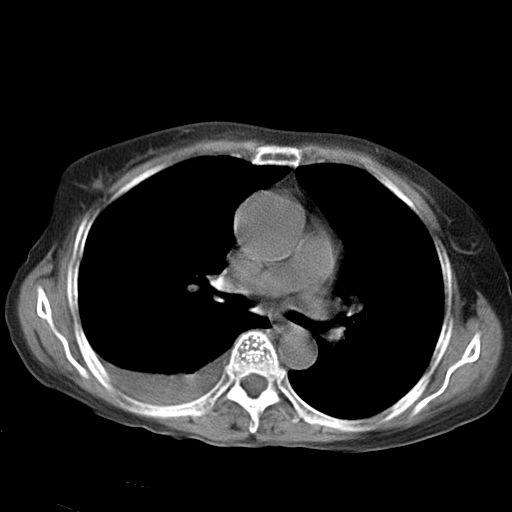

以下是引用dyqct在2006-12-7 21:08:00的发言:[br]考虑:1、肝内外胆管多发性结石伴肝左叶外侧段肝萎缩;[br] 2、右膈下多发脓肿;[br] 3、右侧少量胸腔积液、斜裂积液;[br] 4、左肾囊肿。

以下是引用jiazh在2006-12-7 20:37:00的发言:[br]肝脏周围半狐形低密度影,肝脏表面受压推移,考虑膈下脓肿可能性大;2、右侧胸腔积液

以下是引用拾荒者在2006-12-7 21:44:00的发言:[br]肝内外胆管多发结石,右膈下多发脓肿,右胸膜腔及叶间裂积液,左肾囊肿。[br] [br]